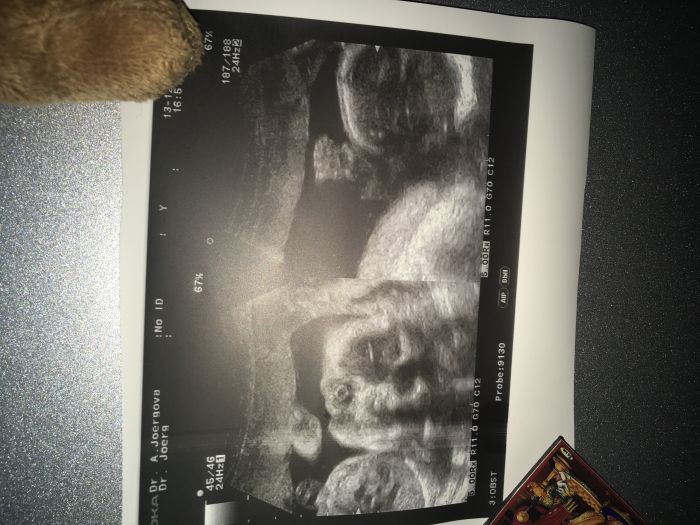

Autor: Verča 1 13.12.2017 v 18:35

Jinak ta první fotecka to je jen rucicka a to druhé zase obličej kdyby se v tom některá z vas nevyznala :-D